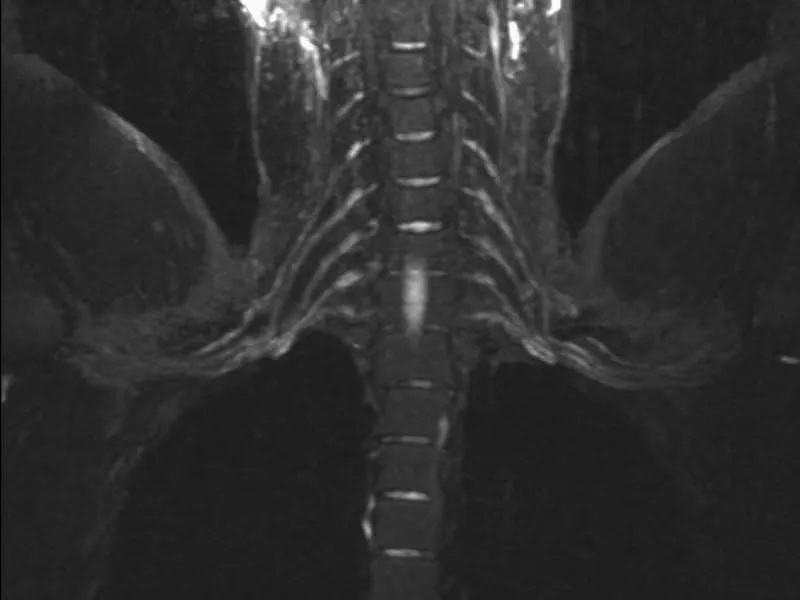

Modern imaging provides essential information in patients with neurogenic TOS. Firstly, imaging tests can directly or indirectly demonstrate compression of veins, arteries or nerves. Second, imaging tests can prove secondary damage to these structures, such as an aneurysm. Third, imaging tests can rule in or rule out blood clots, which are a critical factor in determining treatment. Fourth, imaging tests show multiple points of compression that affect treatment differently. Finally, imaging

The NeoVista® MRI study gives the patient and doctor unique and valuable information. NeoVista® includes separate and detailed images of the soft tissues, nerves, and blood vessels in one comprehensive study. NeoVista® demonstrates changes on arm motion. And NeoVista® is performed by people with world-class knowledge, earned through years of study, experience, and motivation.

Imaging of patients with neurogenic TOS provides valuable information to the TOS specialist. While a TOS specialist may strongly suspect that his or her patient has neurogenic TOS, the clinical examination has poor sensitivity and accuracy. Therefore, several outstanding questions must be answered. Firstly, can compression or tension of the brachial plexus be proven? Second, is there intrinsic disease of the brachial plexus? Third, can alternative diagnoses, such as a herniated disc, be ruled out? Fourth, what are the exact anatomic structures that cause compression or tension of the brachial plexus? Fifth, does arm motion contribute to compression? Finally, what other structures are involved, such as arteries or veins?

Done properly and interpreted by a TOS-specialized radiologist, MRI provides extremely valuable information to the TOS specialist.

It is important to remember that clinical tests used by TOS specialists do not possess very good accuracy. Therefore, while a TOS specialist may suspect neurogenic TOS, he or she cannot easily prove the diagnosis. So, MRI proof of brachial plexus compression or tension provides critical data. Also, rarely, inflammation or trauma of the brachial plexus may cause a similar clinical picture as neurogenic TOS. MRI can clearly rule out such brachial plexus damage.

TOS specialists often find a challenge in distinguishing the symptoms of neurogenic TOS from those caused by cervical spine disease. The NeoVista® MRI examination always includes images of the cervical spine, just for this purpose.

Most neurogenic TOS patients experience symptoms or worsen their symptoms when performing activities. If these changes can be evaluated, conservative treatment plans can be tailored to a specific patient. The NeoVista® MRI uses a proprietary quantitative method of evaluating arm motion on each side, in each patient. We believe this data adds a level of detail that a TOS specialist would find quite important and helpful.

MRI can show the soft tissues of each thoracic outlet in great detail. Scalene muscles and their anomalies, fibrous bands, the brachial plexus and its branches, and the fat that surrounds these structures are very well seen. Bones such as the clavicle, scapula, first rib, cervical rib, and cervical spine can also be seen. MRI can be performed with the arms in different positions. Radiologists can see the changes that arm motion causes.

Obviously, we believe in the value of MRI as the best imaging tool for patients with neurogenic TOS. Further, the test and interpretation of this complex disease should be placed in the hands of experienced TOS specialists. At the risk of sounding biased, we feel strongly that the NeoVista® MRI examination answers each of the important questions in patients with neurogenic TOS, and provides experienced TOS expertise.

The full NeoVista® MRI examination is completed in one visit. It includes detailed images and expert interpretation, including the soft tissues and bones of each thoracic outlet, the cervical spine, the brachial plexus, and the subclavian artery and vein. Arm motion is evaluated and measured. This evaluation can be repeated on follow-up examination. In addition, we support your TOS specialist by offering review and discussion of each case. In many cases, we can provide a video teleconference with your specialist and you, including review of your images.